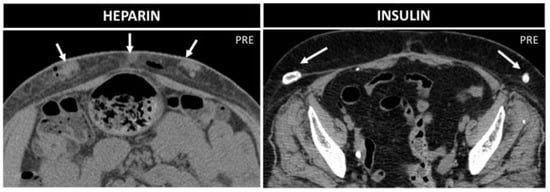

Lipohypertrophy is a classical sequela of subcutaneous insulin injections. On CT and MR, it is seen as focal subcutaneous soft-tissue masses, with fat proliferation in a symmetric fashion [41] and calcifications [41,42,43]. “Insulin balls” can also occur, subcutaneous amyloid deposits, visible as soft-tissue masses, with necrotic borders, due to amyloid toxicity [43] (Figure 14).

Management is different between these two conditions: while lipohypertrophy disappears with the suspension of insulin therapy, insulin balls tend to progressively enlarge and require surgical excision [42]. Repeated heparin injections can be associated with air and fluid levels [9]; small soft-tissue nodules, connected to the destruction of the hypodermic fat; and small hematomas with adjacent hazy soft tissue [44] (Figure 14). There is no special management, only a recommendation to alternate the injection spot when performing heparin injection.

Figure 14. Heparin vs. insulin treatment nodules in two 70-year-old patients. Axial not-enhanced CT in the first patient shows some collections with parenchymatous density, which indicate bleeding, and small air bubbles. In the second patient, instead, lipodystrophies with peripheral calcifications are seen.